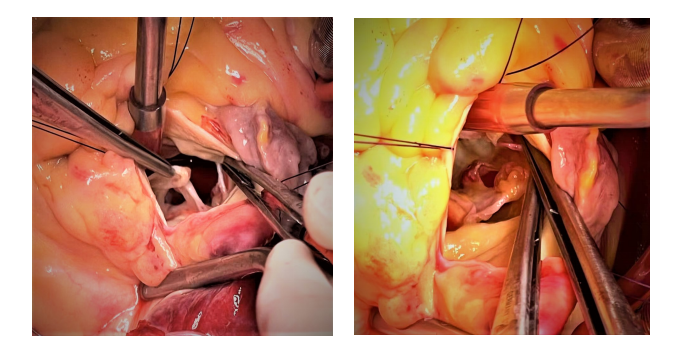

3)2周后,患者体力恢复良好,随即在全麻低温体外循环下行主动脉瓣机械瓣置换术。术中可见升主动脉及主动脉窦部正常,主动脉瓣左冠瓣及无冠瓣均有穿孔。同时,无冠瓣可见赘生物形成。(如图5-A,B)

(图2-A,B)主动脉瓣可见赘生物,舒张期脱入左室流出道。

(图2-C)主动脉瓣大量返流